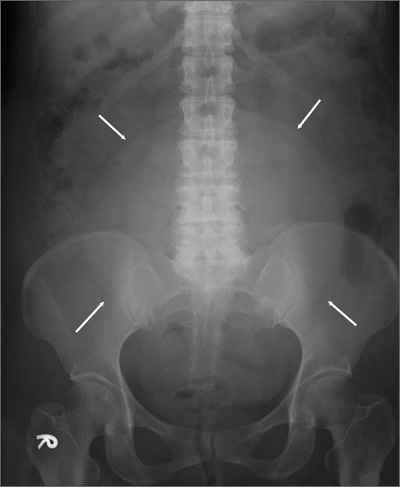

Large pelvic mass

This patient had a large uterine fibroid. Also known as a leiomyoma, a uterine fibroid is a benign tumor that is composed of smooth muscle tissue and fibrous connective tissue. It is the most common pelvic tumor found in the female body. Unlike cancerous tumors, fibroids usually grow slowly and do not break away or invade other parts of the body.

Based on its position within the uterus, a fibroid can be submucosal, intramural, or subserosal. Uterine fibroids are usually diagnosed based on a clinical history and pelvic examination; the presence of a fibroid is confirmed by ultrasound, magnetic resonance imaging, computed tomography, saline infusion sonography, or hysterosalpingography.

This patient’s physicians originally suspected malignancy, so they consulted a gynecologist for a sonographic examination. The ultrasound revealed a heterogeneous mass with calcification. The patient underwent a hysterectomy.

The solitary soft tissue mass that was removed measured 13 cm in diameter and weighted 2100 g. Histopathological analysis revealed that the fibroid was made up of myometrium and fibrous connective tissue. After hospital discharge, the patient resumed all of her normal activities with no recurrence.